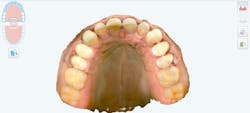

During the initial appointment, the patient stated that his objective was to lessen the amount of gums he displayed while smiling. Records were obtained, including facial photos, intraoral scan, and CBCT. Through quantitative analysis, the height-to-width ratio of his anterior central teeth was nearly 1:1, with the ideal ratio of width to height being 0.80. Also noted was the wear on the teeth. This caused the teeth to be 8 mm in length when they should be between 10 mm and 11 mm.

Utilizing a facially driven treatment plan, the facial photographs were merged with the CBCT scan to assess bone levels, and the central incisors were digitally planned to exhibit a new length of 11.5 mm, to enhance the patient’s long facial structure. The new width of the veneers could then be generated to be 85% of this measurement to achieve the golden proportion for optimal esthetics. Once the surgical guide is designed in Exocad to achieve these coronal margins, the guide design is exported to SprintRay to be printed with a snug fit for accurate coronal margination for the final restorations later on.